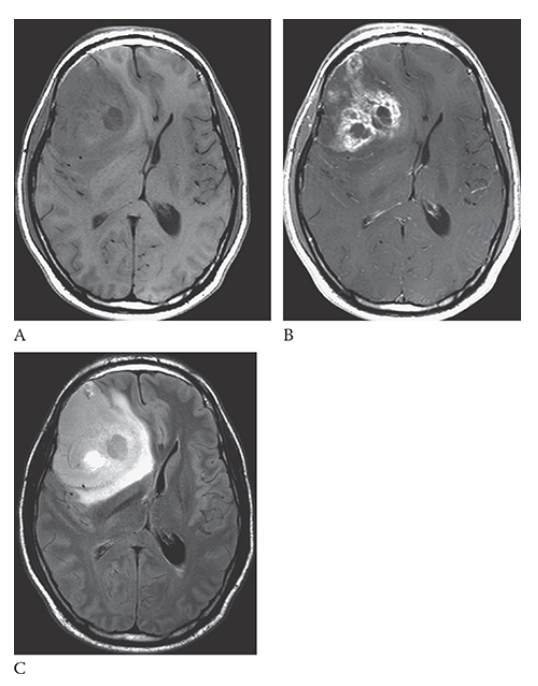

What is A

Glioblastoma Multiforme. shows an isointense mass with low-signal central necrosis and surrounding edema. Postcontrast T1W image

What is B

Glioblastoma Multiforme.hows peripheral irregular enhancement. FLAIR image

What is C

Glioblastoma Multiforme. shows high-signal edema.